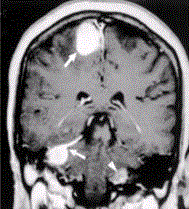

问题 患者男,20岁,头痛、步态不稳。MRI显示如下图。 关于神经纤维瘤病的影像学表现,正确的是

选项 A.Ⅰ型主要累及外周神经的丛状纤维瘤及视神经胶质瘤 B.Ⅱ型可见蝶骨大翼发育不良,眶上裂增宽等 C.皮肤caféanlait斑,腋窝、腹股沟雀斑常见于Ⅱ型 D.Ⅰ型常见多发脑神经鞘瘤、脑膜瘤及脊神经肿瘤 E.NF-2相关的神经鞘瘤较散发的增生活性高而且存在侵袭性

答案 A